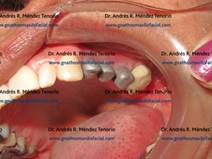

ELEVACION DE SENO MAXILAR E IMPLANTES

Este procedimiento permite colocar implantes dentales en zonas posteriores del maxilar, donde la reabsorción ósea no permite la colocación de implantes. El límite anatómico aquí es el piso del seno maxilar, que al injertarse con hueso proporciona la longitud suficiente para restaurar con implantes

| ||

![]() |

|

| Vista preoperatoria de paciente con ausencia de molares superiores izquierdos y esquema del defecto | ||

||

| Momento de la elevación del piso de seno y colocación del injerto óseo | ||

| Inserción de los implantes y colocación del restante de injerto óseo alrededor de ellos | ||

| Cuatro meses después los implantes se han integrado, y se prueban las partes de las coronas que se soportarán sobre ellos | ||

| Resultado final de la restauración terminada | ||

| Radiografías antes y después del proceso | ||